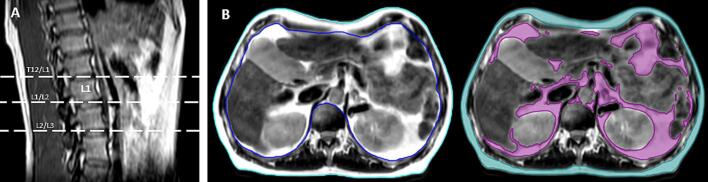

AT was delineated by a single observer (MD), using the Raystation (V12, Raysearch Labs, Stockholm, Sweden) system at three anatomical points: the intervertebral disc between the 12th thoracic vertebra (T12) and 1st lumbar vertebra (L1); between L1 and 2nd lumbar vertebrae (L2); and between L2 and the third lumbar vertebra (L3) (Fig. 1a). SAT and VAT were delineated on the free-breathing T2W scans, to avoid distortion of anatomy by the abdominal compression belt. SAT was manually delineated using the Smart Contour tool, and VAT using participant-specific automatic signal intensity thresholding, visual inspection, and manual editing where required.

Fig. 1.

Example of delineation borders for A. anatomical points for measurement, and B. external patient contour (cyan), internal patient contour (blue), SAT (teal), and VAT (purple).

External and internal contours were delineated: external defined as the external border of the patient surface, and internal defined as the internal border of the ribcage (Fig. 1b). Structure volumes were calculated automatically by the system and recorded. AT was defined as the percentage of internal/external contour attributable to fat: %AT = AT volume (cm3) divided by external/internal patient volume (cm3).